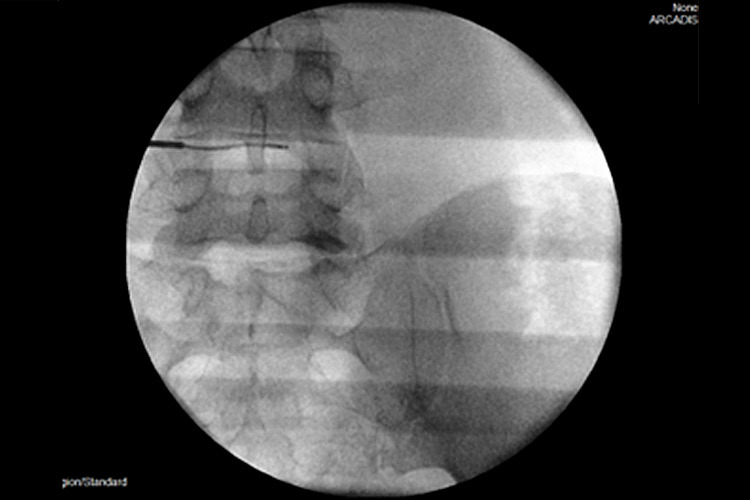

Χρησιμοποιώντας την εφαρμογή ραδιοσυχνοτήτων, εισάγεται, αρχικά, ένας οδηγός κάτω από ακτινοσκοπικό έλεγχο στον μεσοσπονδύλιο δίσκο και κατευθύνεται έμπροσθεν της κήλης. Μέσα από τον οδηγό εισάγεται ένα ηλεκτρόδιο, που η άκρη του έχει τη δυνατότητα κίνησης και στροφής 360ᵒ (Σχ. 1).

Το ηλεκτρόδιο υπερθερμαίνεται μέσα από μια πηγή σε θερμοκρασία 40ᵒC - 70ᵒC (coblation – low temperature ablation). Είναι μια μέθοδος, που χρησιμοποιεί ηλεκτρόδιο ραδιοσυχνοτήτων σε χαμηλές θερμοκρασίες για σύντομο χρονικό διάστημα 2’- 3’, χωρίς να καταστρέφει τους παρακείμενους ιστούς, αλλά δρα μόνον στο επιθυμητό σημείο του μεσοσπονδύλιου δίσκου (Σχ 2).

Σχ. 2 Η εισαγωγή του ηλεκτροδίου (RF), δημιουργεί ένα κενό, που βοηθάει στην «ανάταξη» της προβολής του δίσκου.

Περίπτωση 1: Ακτινοσκόπηση σε Διαδερμική Δισκοπλαστική με χρήση ηλεκτροδίου (RF) σε κήλη μεσοσπονδυλίου δίσκου Ο4-Ο5. |